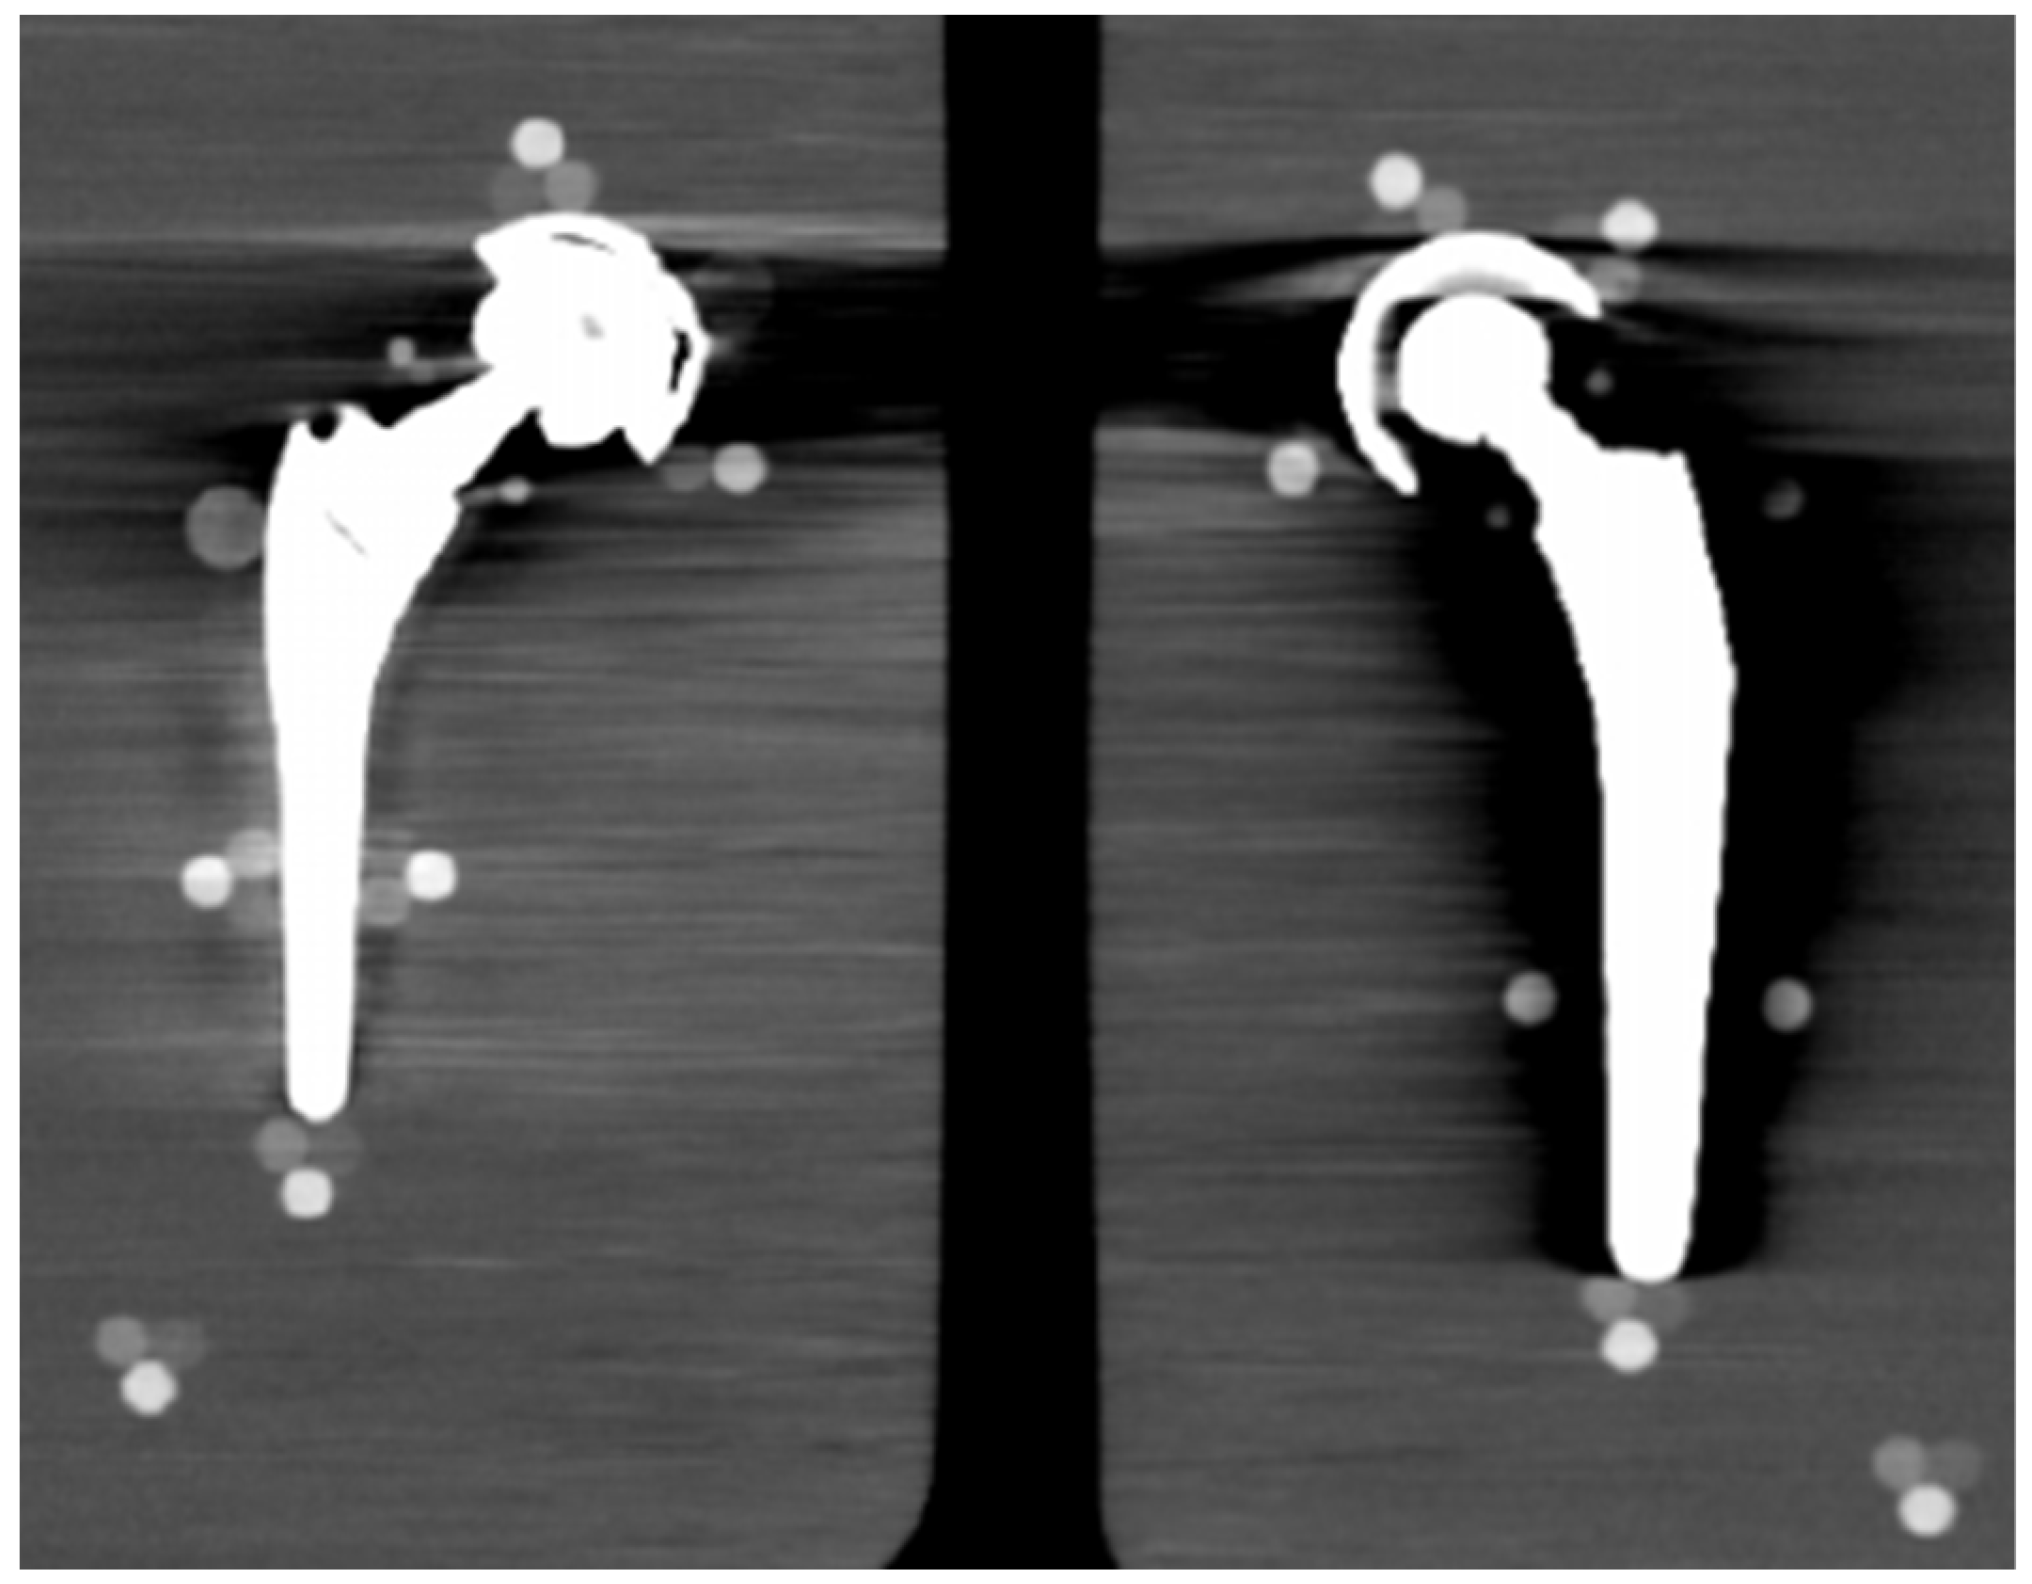

2.2. Hip Phantom and Prostheses

| Configuration | Right Side | Left Side |

|---|---|---|

| Reference | NO PROSTHESIS | NO PROSTHESIS |

| TI | Stem: Ti6Al4V Cup: Ti6Al4V Insert: zirconia toughened alumina Head: zirconia toughened alumina | NO PROSTHESIS |

| CO cem. | Stem: CoCrMo cemented Cup: Ti6Al4V Insert: UHWMPE Head: CoCrMo | NO PROSTHESIS |

| CO | Stem: CoCrMo Cup: stainless steel Insert: UHWMPE Head: CoCrMo | NO PROSTHESIS |

| SS | Stem: stainless steel Cup: stainless steel Insert: UHWMPE Head: stainless steel | NO PROSTHESIS |

| TI+SS | Stem: Ti6Al4V Cup: Ti6Al4V Insert: zirconia toughened alumina Head: zirconia toughened alumina | Stem: stainless steel Cup: stainless steel Insert: UHWMPE Head: stainless steel |

| CO+SS | Stem: CoCrMo Cup: stainless steel Insert: UHWMPE Head: CoCrMo | Stem: stainless steel Cup: stainless steel Insert: UHWMPE Head: stainless steel |

| CO+TI | Stem: CoCrMo Cup: stainless steel Insert: UHWMPE Head: CoCrMo | Stem: Ti6Al4V Cup: Ti6Al4V Insert: zirconia toughened alumina Head: zirconia toughened alumina |